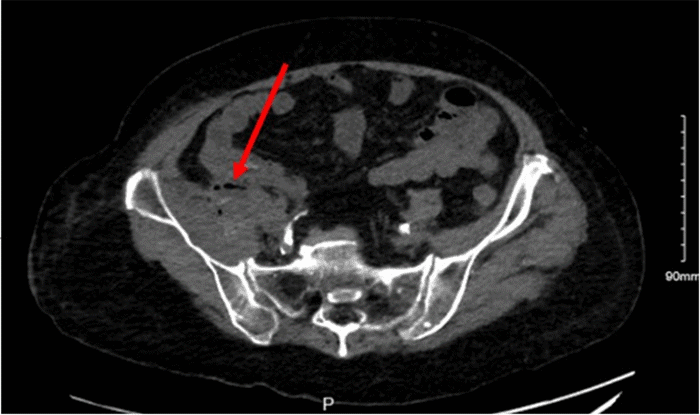

Computed tomography (CT) of the abdomen and pelvis demonstrated inflammation and gas within the right pelvic wall with 5 cm of complex fluid collection (Figure 2), and gas tracking along the psoas and iliacus muscles (Figures 3 and 4), suggestive of septic shock secondary to NSTI. Given the patient’s clinical presentation of septic shock, aggressive management was initiated with intravenous fluid resuscitation, broad-spectrum antibiotics, and reversal of coagulopathy using prothrombin complex concentrate and vitamin K. Subsequently, the patient underwent emergent surgical exploration and debridement of the infected right groin region.

Figure 4. Gas and Heterogeneity in Iliacus Muscle. Published with Permission

CT Abdomen and Pelvis showing small bubbles of gas and heterogeneity of the iliacus muscle as well as gas in the right abdominal wall.